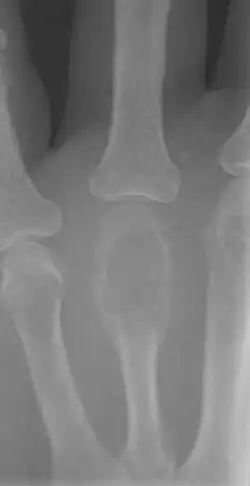

A bone tumor is an abnormal growth of tissue in bone, traditionally classified as noncancerous (benign) or cancerous (malignant).[1][4] Cancerous bone tumors usually originate from a cancer in another part of the body such as from lung, breast, thyroid, kidney and prostate.[1] There may be a lump, pain, or neurological signs from pressure.[1] A bone tumor might present with a pathologic fracture.[1] Other symptoms may include fatigue, fever, weight loss, anemia and nausea.[2][3] Sometimes there are no symptoms and the tumour is found when investigating another problem.[2][3]

Diagnosis is generally by X-ray and other radiological tests such as CT scan, MRI, PET scan and bone scintigraphy.[1] Blood tests might include a complete blood count, inflammatory markers, serum electrophoresis, PSA, kidney function and liver function.[1] Urine may be tested for Bence Jones protein.[1] For confirmation of diagnosis, a biopsy for histological evaluation might be required.[1]

A bone tumour may be felt on examination, following which a plain X-ray is usually carried out.[1][15] Blood tests might include a complete blood count, inflammatory markers, serum electrophoresis, PSA, kidney function and liver function.[1] Urine may be sent for Bence Jones protein.[1] Other tests that might be requested include a CT scan, MRI, PET scan and bone scintigraphy. For confirmation of diagnosis, a biopsy for histological evaluation might be required, using either a needle or by incision (open biopsy).[1][2]